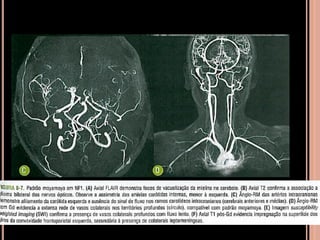

 Alterações cerebrovasculares são incomuns;

 Estenose, aneurismas; malformações

arteriovenosas, hipoplasia das artérias carótidas

internas;

NF1

 Difusão importante para detectar isquemia

parenquimatosa aguda;

 Neurofibromas:

tu benignos da bainha dos nervos periféricos que

podem se originar desde a raiz dorsal dos gânglios

nervosos até os ramos nervosos terminais de

qualquer nervo;

Cutâneo, subcutâneo, nodular profundo e

plexiforme(NFP);

NFP

 Crescimento longitudinal ao longo dos nervos

 Até em 50% dos pacientes com NF1

 10% sofrem transformação maligna;

 Meningoceles e cistos aracnoideos: nos forames

intervertebrais ou adjacentes às vértebras

remodeladas;

 Neurofibromas paraespinais: comprometem a raiz

nervosa;

 Neurofibromas iso ou hipossinal em T1 e hipersinal

em T2 e intensa impregnação pelo contraste;

“sinal do alvo” em T2;

 Tu intramedulares são incomuns: maioria é glioma;